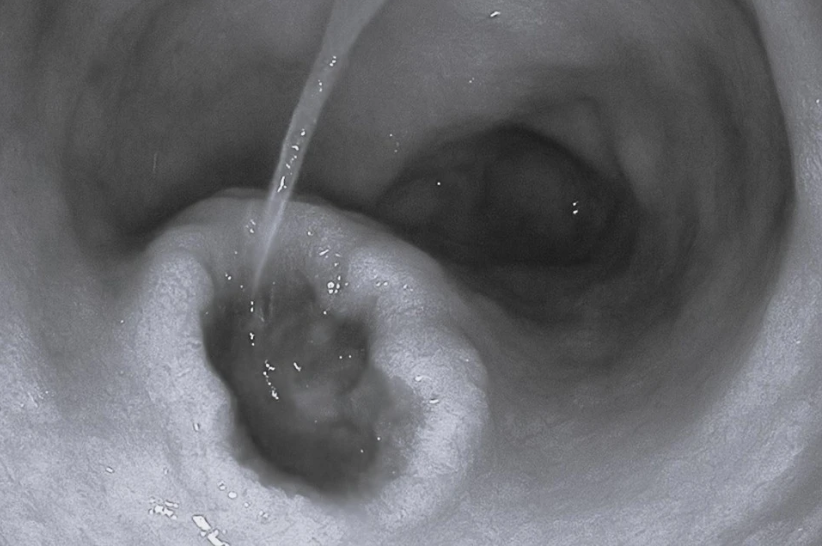

Nhiều người nhập viện trong tình trạng xuất huyết tiêu hóa do lạm dụng thuốc giảm đau. Ảnh: BVCC.

Thời gian gần đây, các bác sĩ khoa Nội Tiêu hoá của Bệnh viện Đa khoa tỉnh Tuyên Quang liên tục tiếp nhận nhiều bệnh nhân nhập viện trong tình trạng xuất huyết tiêu hoá hoặc xuất hiện hội chứng Cushing sau khi tự ý dùng thuốc giảm đau và thuốc chống viêm.

Các bác sĩ cho biết nhiều trường hợp rơi vào tình trạng rất nặng, điển hình như xuất huyết tiêu hoá do loét dạ dày - tá tràng khiến người bệnh nôn ra máu, đi ngoài phân đen và nhanh chóng trụy mạch nếu không được cấp cứu kịp thời. Một số ca còn tiến triển đến thủng tạng rỗng, phải phẫu thuật cấp cứu.